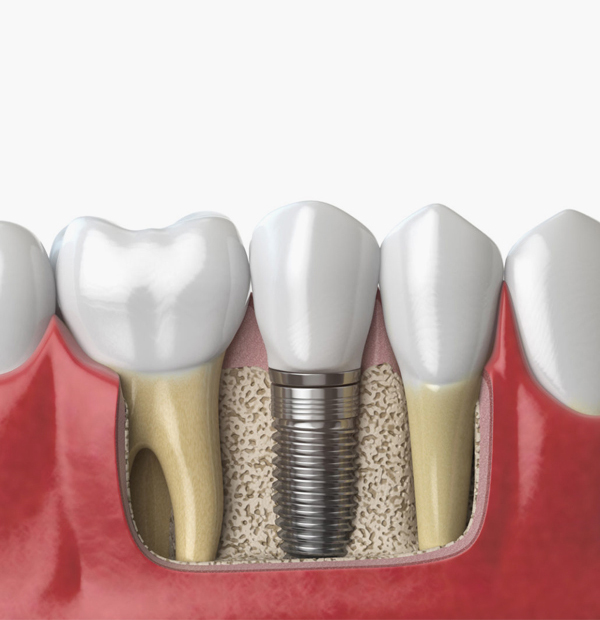

Cost of Dental Implant